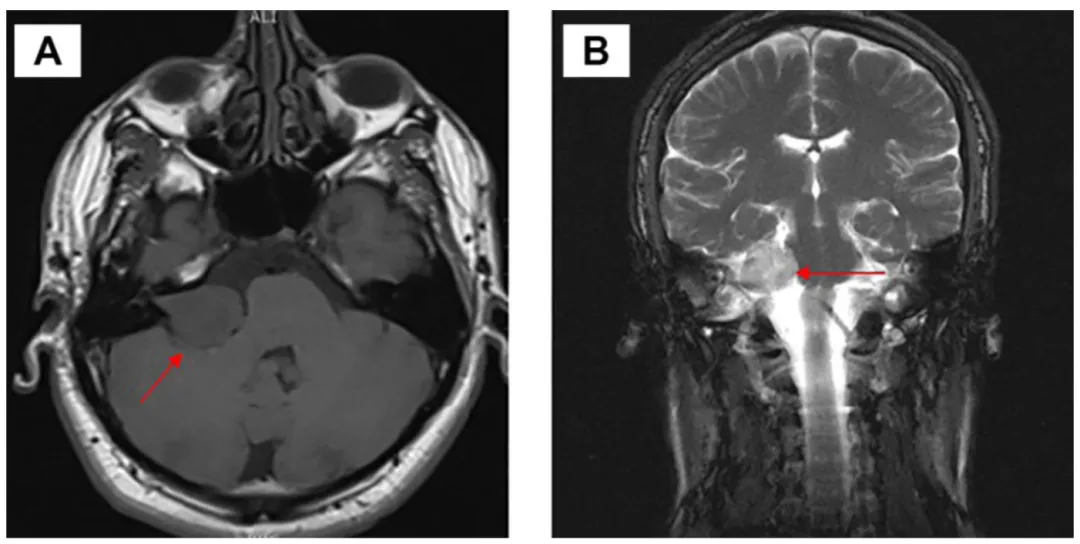

磁共振成像(A)轴位面与(B)冠状位面图像显示,右侧前庭神经鞘瘤主要位于右侧桥小脑角区,并向内听道内延伸。扫描可见肿瘤对右侧三叉神经构成明显压迫,并对脑干产生轻微压迫(图中红色箭头指示)。